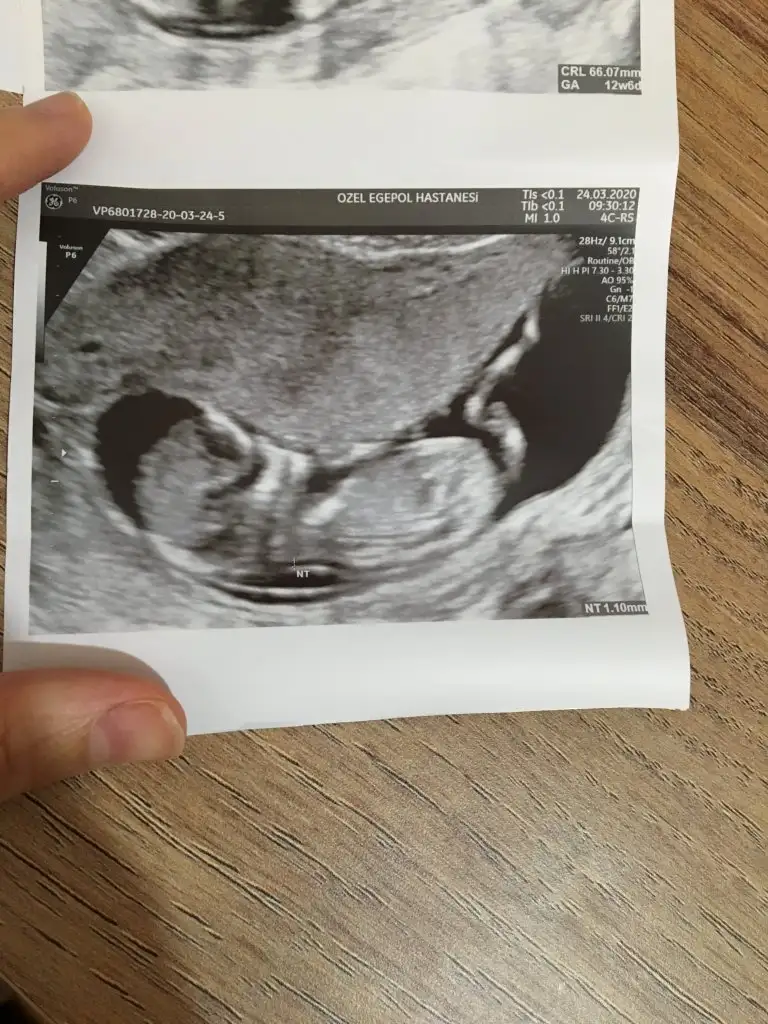

Merhaba bana da tahmin yapabilir misiniz dosya ekledim 12+6 ya ait ultrason görüntüsü

11 haftalık ultrason yorumlar misiniz acaba

Kız gibi emin olamıyorum nubu ne dik nede paralel böyle usgler beni yanıtıyor hatta iki usg paylaşıldı onlarada tahminimde yanılma olabilir dedim 😂😂 B BUSR4 ve A Aselberen usgleri de böyle nubları umarım yanılmıyorumdur sanki eminde değilim kız gibi gibi 😬😬